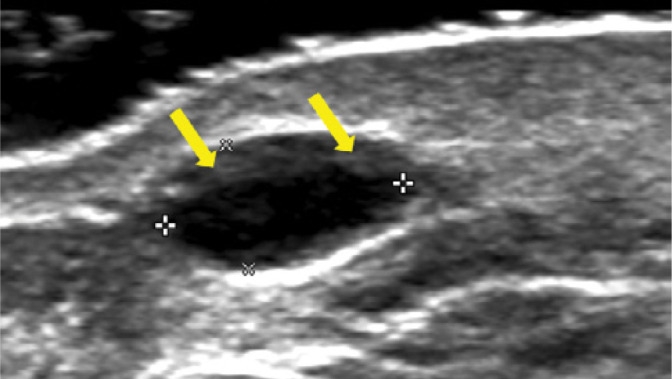

臨床治療上,我喜歡用超音波來精準判讀,(上圖)影像可見皮下組織內一個邊界清楚的橢圓形低回音/近無回音(Anechoic)囊樣結構(黃箭頭處),符合玻尿酸HA殘留或局部聚集,用於評估打針硬塊消不掉時是否仍有可被定位的HA,並作為後續導引處置參考。